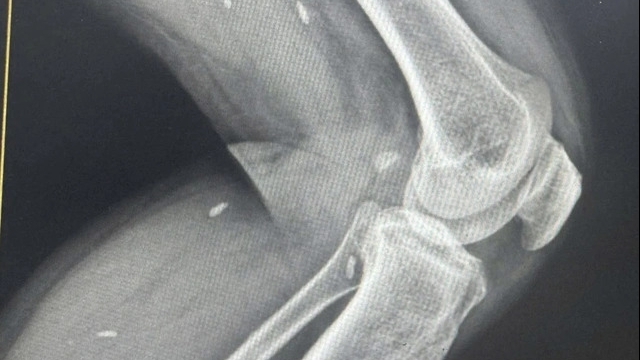

Khi đưa con đi khám mắt, hai vợ chồng choáng váng khi con gái bị chẩn đoán cận thị nặng, gần 9 đi-ốp. Các bác sĩ cho biết tình trạng này không thể cải thiện và thị lực của cô bé có thể trở nên tồi tệ khi bé lớn lên.

Bác sĩ nhận định trường hợp của bé Xiao Man là do sử dụng thiết bị điện tử kéo dài và quá sớm.